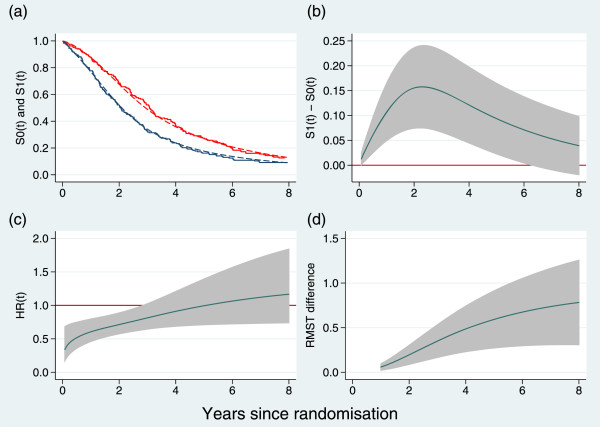

An example of a graphic illustrating the four outcomes for the GOG111 trial in ovarian cancer [9] is shown in Figure 1. The estimates are plotted on a continuous time-scale to avoid imposing arbitrary cut-points. We have truncated the estimates in Figure 1 to 8 years’ follow-up since there is almost no data beyond this point. Having sufficient follow-up is critical to obtaining reliable clinical and statistical assessment of a treatment’s effectiveness but is rarely emphasized in trial reports.

Figure 1.

Time-dependent outcome measures exemplified by the GOG111 trial in advanced ovarian cancer. (a) Kaplan-Meier curves (solid lines) and estimated survival functions (dashed lines) from a flexible parametric model; (b) difference in survival functions; (c) instantaneous hazard ratio; (d) difference in restricted mean survival time. Shaded areas are pointwise 95% confidence intervals. Estimates in panels (b), (c) and (d) are derived from a flexible parametric model.

Figure 1(c) indicates that the treatment effect on the relative hazard scale is largest near t=0 and dwindles to HR =1 by about t=4 yr. The survival curves do not cross within the interval (0,8) yr, so the RMST difference, which is the integrated difference between the survival curves, increases in a monotone fashion. By t=8 yr it reaches about 0.8 yr, albeit with a wide confidence interval.

We propose that the primary quantitative estimates are taken as the overall HR with its confidence interval (noting that the instantaneous HR may be time-dependent) and the difference(s) in restricted mean survival time, with confidence interval(s).

The report of quantitative results should include the P-values from each of the three tests (the joint test and its two components), the joint test being the primary comparison and the two components as supporting evidence. The HR from a Cox model and results from Figure 1 at one to three clinically relevant time-point(s) should also be reported.

For advanced ovarian cancer, for example, reporting estimates at 2 and 5 years after randomization might be appropriate. The overall hazard ratio and the test results for the GOG111 trial are shown in the first row of Table 1. The joint test statistic is highly significant (P=0.0004), more so in fact than either of its components.

Estimates of key quantities at 2 and 5 years of follow-up are given in Table 2. There is a fairly substantial treatment effect. For example, the RMST difference is ≥10% of the reference follow-up time t∗ at both 2 and 5 yr.

Table 2.

Time-dependent quantitative results for the GOG111 trial

| Quantity | t=2 yr | t=5 yr | ||

|---|---|---|---|---|

| Est. | 95% CI | Est. | 95% CI | |

| HR (t) | 0.71 | (0.57,0.89) | 0.99 | (0.71,1.39) |

| S 0(t) | 0.52 | (0.46,0.58) | 0.18 | (0.13,0.23) |

| S 1(t) | 0.68 | (0.62,0.73) | 0.27 | (0.22,0.33) |

| S 1(t)-S 0(t) | 0.16 | (0.07,0.24) | 0.09 | (0.02,0.16) |

| RMST 0 (yr) | 1.53 | (1.45,1.61) | 2.44 | (2.22,2.67) |

| RMST 1 (yr) | 1.73 | (1.66,1.79) | 3.04 | (2.81,3.26) |

| RMST 1- RMST 0 | 0.20 | (0.09,0.30) | 0.59 | (0.27,0.91) |

Note that the estimated hazard ratio, HR(t), is instantaneous. See text for further details.